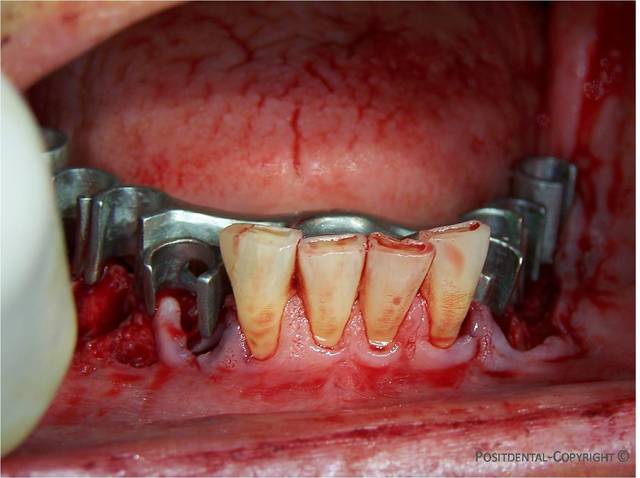

30/04/2010 à 11h44

le rouge aussi

Image7 lpqmzc - Eugenol